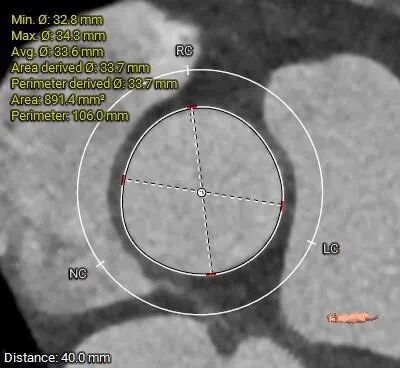

• 三叶式主动脉瓣,瓣叶增厚,R-L交界增厚粘连,轻度钙化,钙化主要沿无冠窦瓣缘分布;LVOT近似直筒型;

• 瓦氏窦内径尚可,STJ小于30mm,升主动脉无扩张,瓣上40mm处测得约33.7mm;

主动脉根部评估

瓣上多平面分析